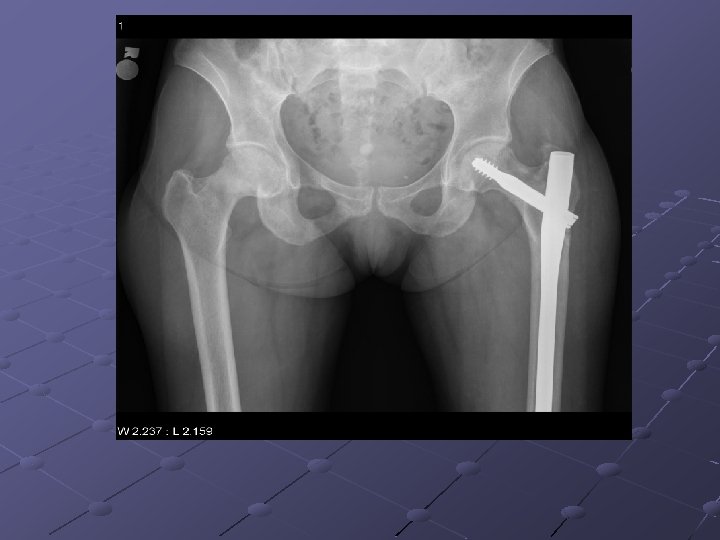

Imaging Studies